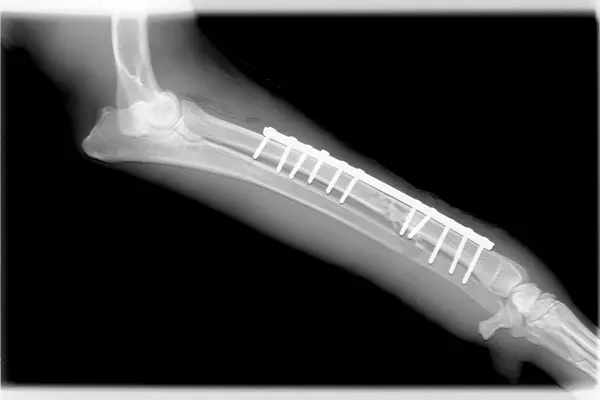

Los especialistas examinaron una serie de implantes, como tornillos utilizados en intervenciones quirúrgicas, e identificaron bacterias y hongos en ellos, a pesar de que los pacientes no han mostrado signos de infección.

Los aditamentos estudiados van desde tornillos y rodillas, hasta marcapasos y se trabajó con pacientes de cinco hospitales de la capital de Dinamarca, en diferentes grupos: con aflojamiento aséptico (cirugías de cadera), implantes craneofaciales, fracturas curadas y recién enfermos con implantes.

De las prótesis examinadas, la mayoría de los tornillos habían sido colonizados por bacterias, y en todos los casos ninguna de las bacterias u hongos eran patógenos como el estafilococo.